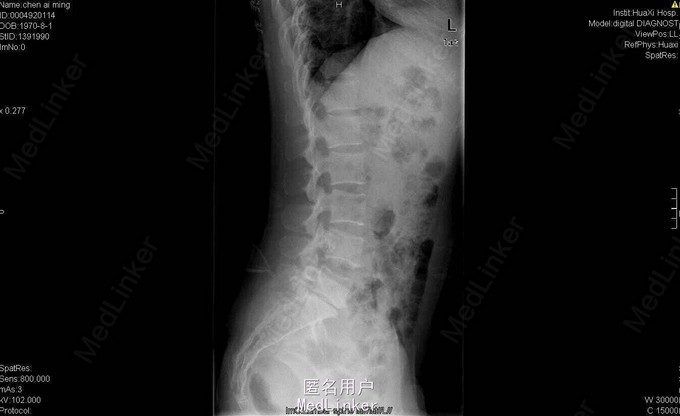

女,40岁2月,因“腰部反复疼痛2+年,加重伴双下肢疼痛、麻木1+年”入院。视:脊柱外观无畸形,皮肤未见红肿、皮疹、破溃、色斑等,无明显包块。触:腰5骶1椎棘突压痛,椎旁肌压痛,无放射痛。腰骶部感觉麻木。双下肢小腿外侧及足背感觉减退,右侧明显,其余肢体感觉正常,肌张力正常。鞍区右侧感觉减退。双下肢足背动脉搏动好。皮温正常。双膝腱减弱,踝阵挛、髌阵挛(-),巴氏征(-),右下肢直腿抬高试验(30°),直腿抬高加强试验(+),左下肢直腿抬高试验(-)。“4”字征阴性。动量:腰部不能屈伸活动,侧弯可,双下肢活动度正常,四肢肌力正常。CT及MRI:腰5骶1椎间盘脱出,腰4-5椎间盘轻度膨出,硬膜囊受压;腰5骨质增生。腰5骶1椎间盘突出症伴小关节退变。双侧椎板开窗腰5骶1椎间盘髓核摘除、内固定术。